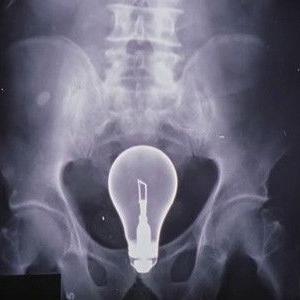

Molly travaille sur la résolution des conflits en milieu hospitalier et choisit le docteur Cox comme sujet d'étude. Pourvue de bonnes intentions, elle tente de réconcilier JD et Elliot, en compétition pour décrocher le poste de Chef des internes. Pendant ce temps, Cox, JD et le concierge essaient de résoudre le mystère de l'hôpital : comment extraire une ampoule du ventre d'un patient sans la briser ?